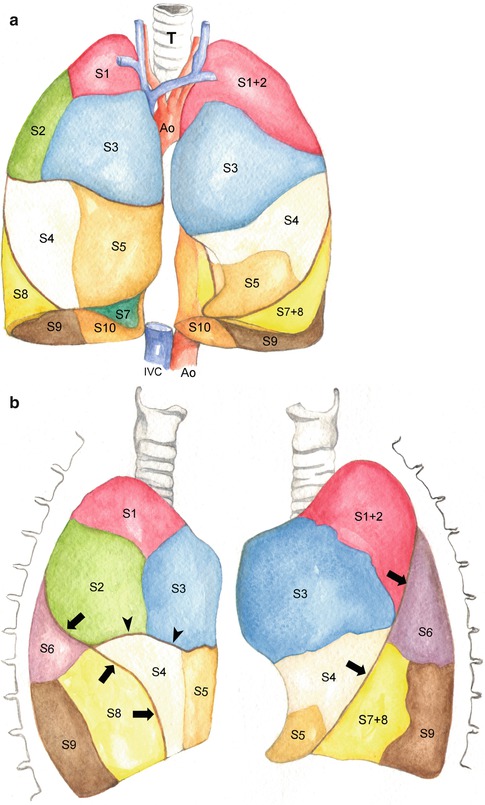

Анатомические изображения сегментов легких различных животных

Раздел: Другие животные